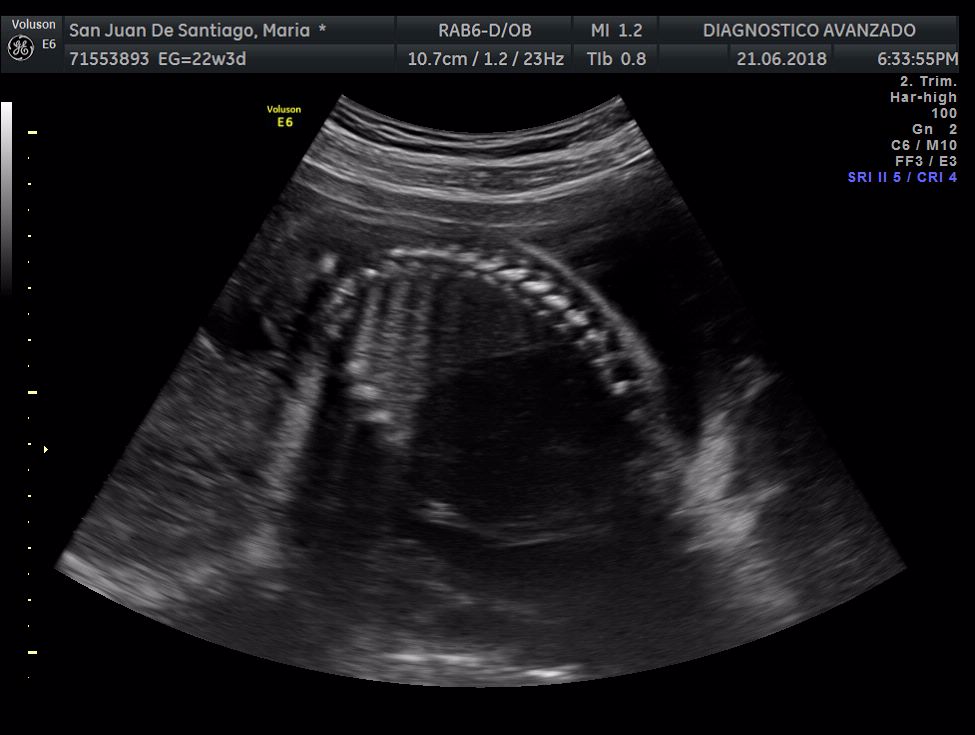

¡Hola a todos! Hoy hemos ido a hacer la tradicional ecografía 3D de la niña, os dejamos todo el material (aunque es un poco demasiado).